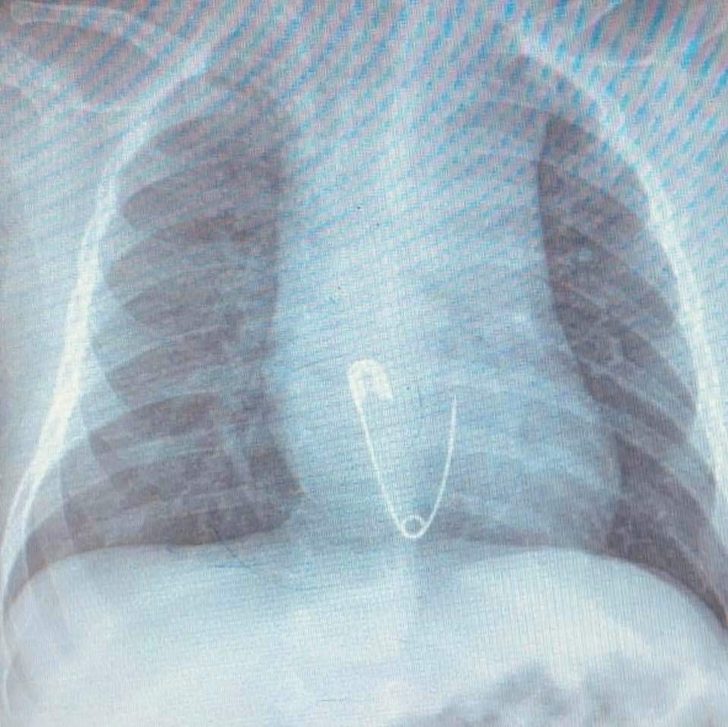

Diyarbakır’da ikamet eden Esvet ile Amine Solmaz çiftinin tek çocukları olan 5 aylık Efraim’in nefes borusuna ailenin taktığı çengelli iğneli nazar boncuğu kaçtı. Aile bebeklerinin ağzına kaçan nazar boncuğunu çıkardı ama çengelli iğneyi çıkaramayınca en yakın hastaneye başvurdu. Burada yapılan ilk müdahalenin ardından bebek Elazığ’a sevk edildi. Ambulansla Fırat Üniversitesi (FÜ) Hastanesi Çocuk Gastroenteroloji Hepatoloji ve Beslenme Bölümü’ne getirilen bebeğin yapılan tetkiklerinde iğnenin yemek borusunun alt kısmında takılı kaldığı tespit edildi. Hemen Çocuk Endoskopi Ünitesine alınan bebeğin nefes borusundaki iğne, yapılan endoskopik yöntemle yaklaşık 15 dakikalık sürede çıkarıldı. Sağlık durumu iyi olan bebek ve ailesi taburcu edildi.

Hastanın Diyarbakır’dan Elazığ’a geldiğini belirten Prof. Dr. Yaşar Doğan, “Hastayı kabul ettik, 5 aylık bir hasta. Bize gelmeden önce üzerinde bulunan nazar boncuğunu çengelli iğne ile birlikte ağzına götürmüş. Aile de fark edince müdahale etmiş, ağzındaki nazar boncuğunu çıkarmış fakat o esnada çengelli iğne yemek borusuna kaçmış. Hasta geldiği zaman çektiğimiz röntgende çengelli iğne yemek borusunun alt kısmında takılı vaziyetteydi. Hastaya 15 dakikalık sedasyon altında işlem yapıldı, endoskopi ile parça çıkarıldı. Hasta şu anda gayet iyi. Biraz sonra da evlerine göndereceğiz” dedi.